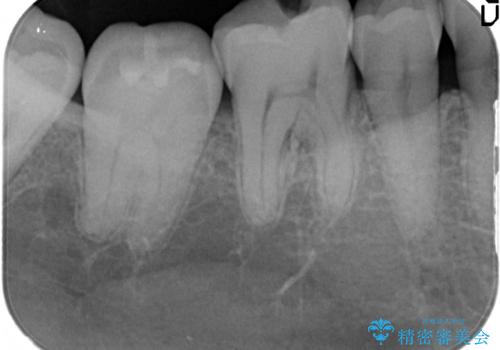

治療したむし歯の再治療。セラミックにしたい!

- 以前治療した歯が欠けたことを主訴に来院されました。

見た目もよく強度の高いものでの修復を希望されましたのでセラミックインレーにて修復しました。

当院でのセラミックインレーは歯とのつなぎ目を拡大鏡で確認して精度高く仕上げるため、むし歯のリスクを限りなく少なくできるよう治療します。